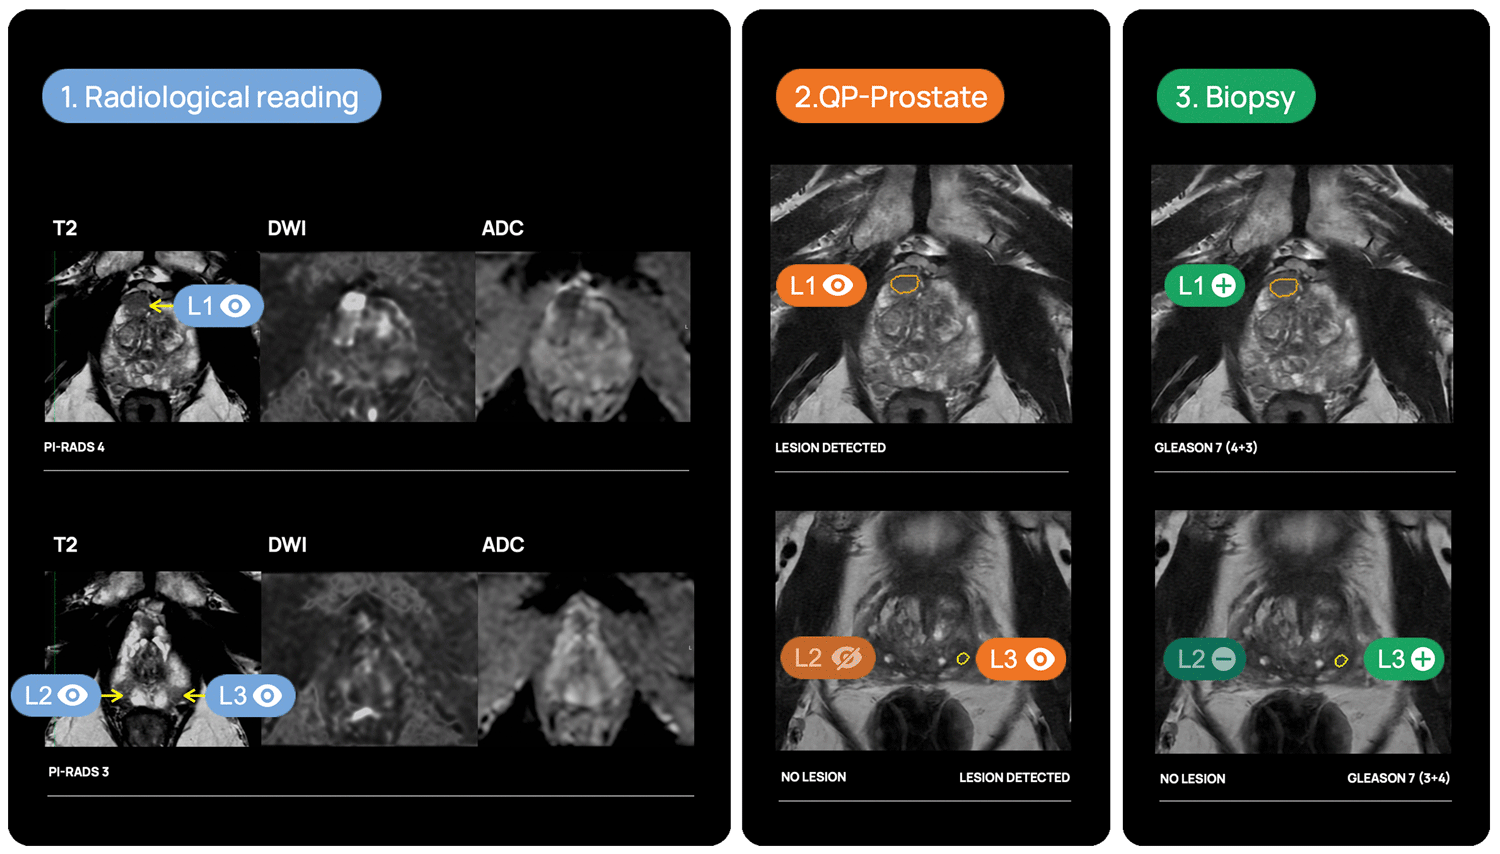

QP-Prostate is setting a new standard for accuracy, speed, and diagnostic precision. Its AI algorithm identifies and stratifies by likelihood intermediate and high-grade aggressive prostate cancer lesions, and provides a segmentation of the prostate. This allows Health Care Professionals to improve their diagnostic accuracy and fusion biopsy planning.

Lesion detection & diagnosis

QP-Prostate automatically identifies and highlights prostate regions suspicious for aggressive prostate cancer, assigning each a confidence-based classification score.

Fusion biopsy planning

QP-Prostate is fully integrated into most of the fusión biopsy devices, to allow a more accurate targeted biopsy.